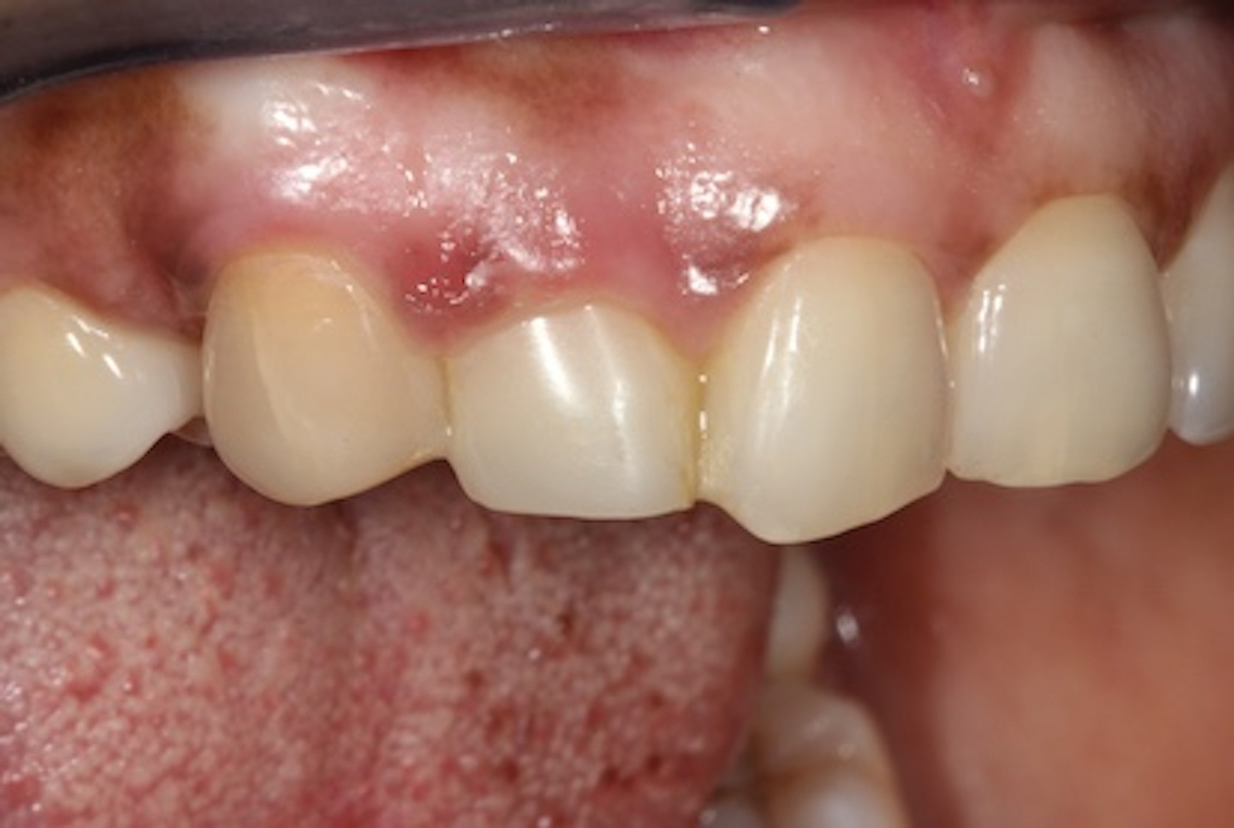

(2.) Close-up right lateral view of the tooth No. 7 site following extraction and implant placement.

Figure 2

In the example case presented, the patient returned for evaluation 3 months after implant placement and delivery of the fiber-reinforced composite bridge, and the soft tissue at the site demonstrated adequate growth over the resin pontic (Figure 14). This would provide for a favorable esthetic outcome when the final implant-supported crown was ultimately delivered.